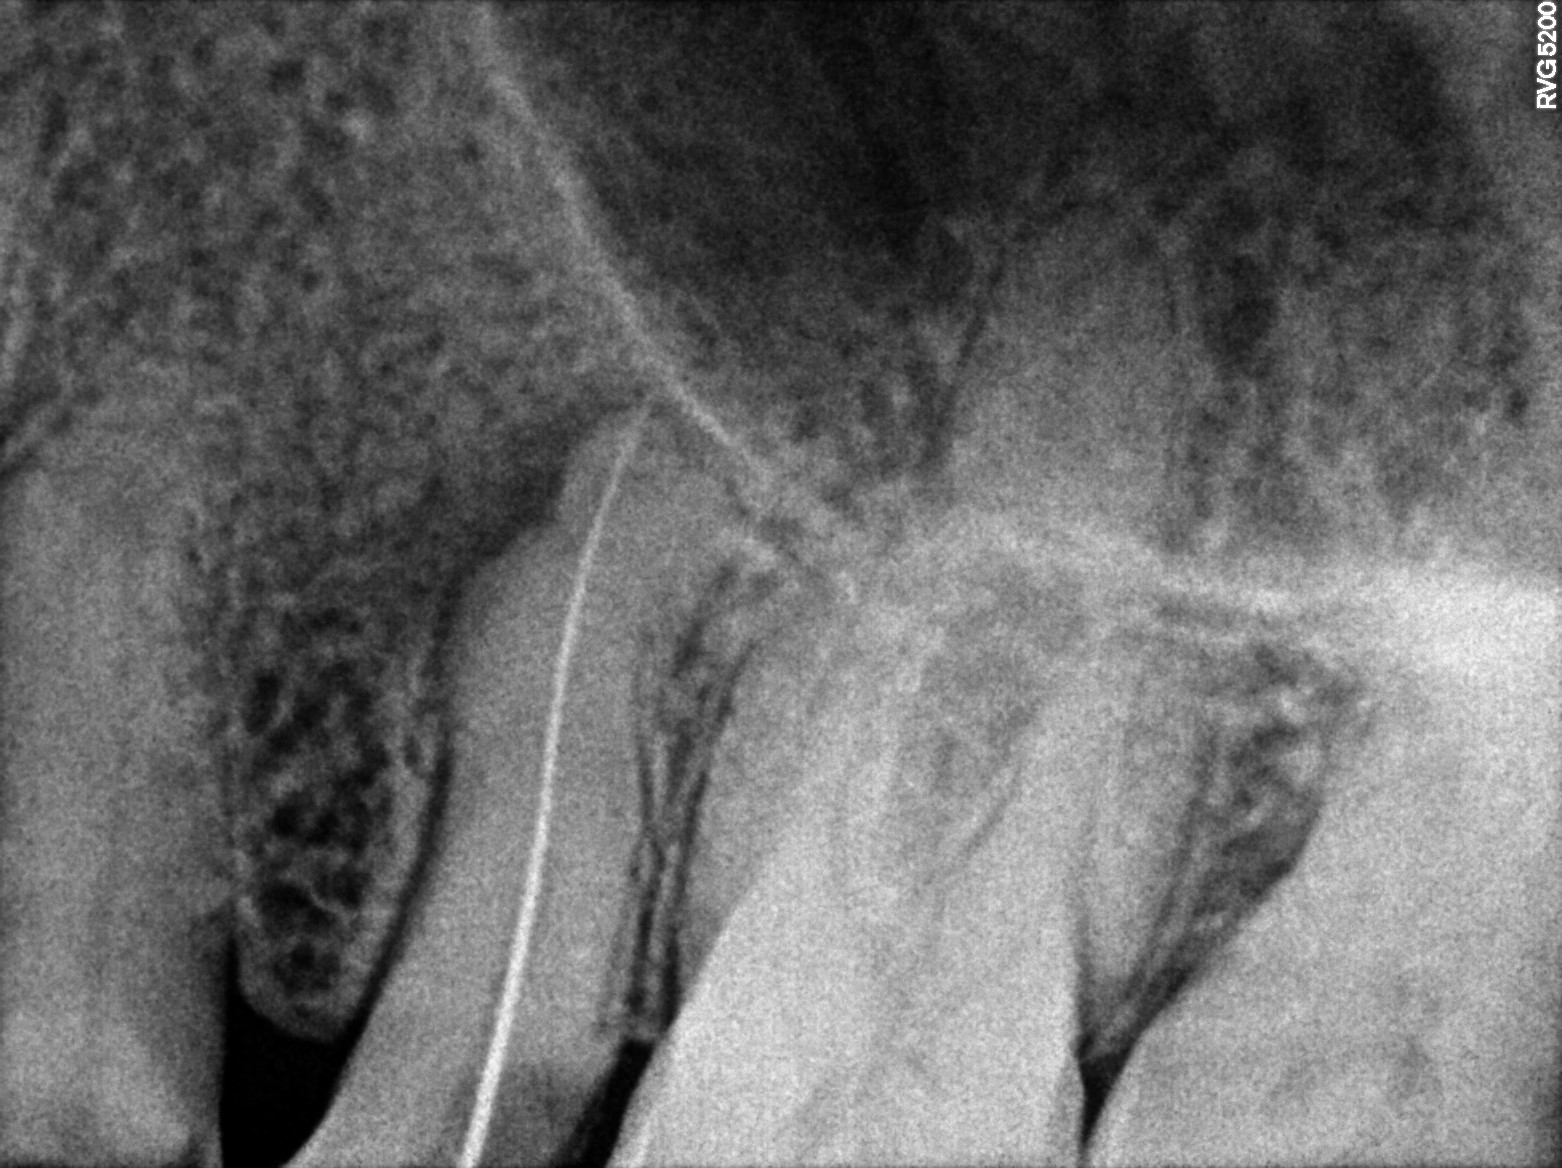

Dental Radiographs FHIR: DocumentReference · LOINC 24641-7

R55.jpg

24641-7